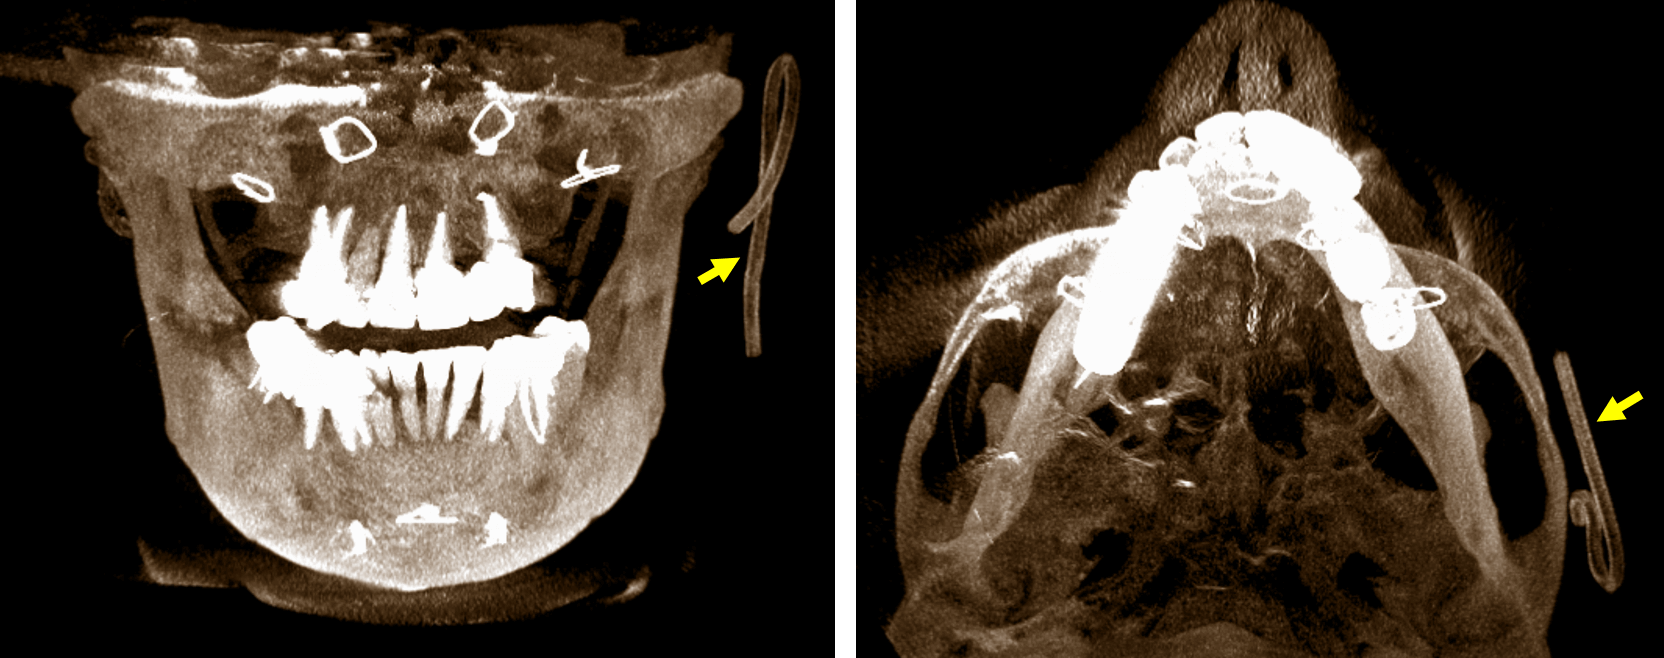

Fig.4

En la reconstrucción tridimensional (Fig.4) se observa se forma didáctica el hallazgo tomográfico el cual se observa que hace una curva a nivel superior compatible con un catéter.